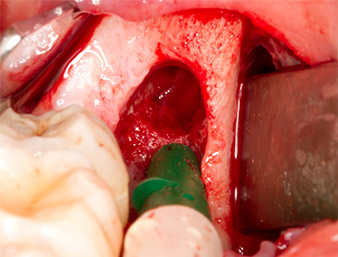

Um autogenes Material für die spätere Wundversorgung zu gewinnen, wurden mit einem piezochirugischen Instrument (Piezomed B5) gesunde Knochenspäne aus der Umgebung des Wurzelrests gewonnen (Abb. 5).

Piezomed B5

Abb. 5: Mit einem meißelförmigen piezochirurgischen Instrument (Piezomed B5) wird Knochen im Bereich der Alveole abgehoben. Dieser dient nach Entfernung des Wurzelrests als autologes Augmentationsmaterial

(vgl. Abb. 13 und 14).

Das autogene Gewebe wurde mit dem schaufelförmigen Arbeitsteil des Instruments entnommen und bis zur weiteren Verwendung in physiologischer Kochsalzlösung aufbewahrt (vgl. Abb. 13).